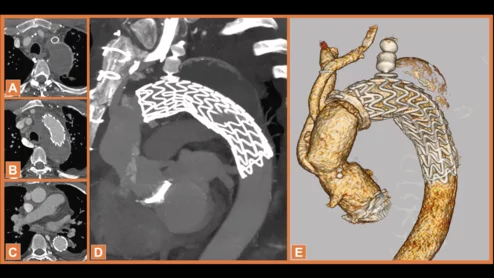

elephant trunk (FET) technique to treat a middle-aged heart patient, sharing their experience in JACC: Case Reports.[1] This is believed to be the first time surgeons have ever employed this particular approach.

When the devices needed for a specific procedure were not available, a group of surgeons got creative. Their one-of-a-kind approach was a success, and the patient has experienced no complications.